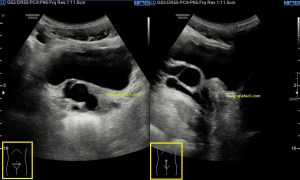

Correspondencia en eje largo al corte de la imagen 3, observa el abombamiento selectivo del retináculo. El tendón también grande respecto a la imagen contralateral. Te marco ambos tendones, para que observes el cambio de calibre.

Detalle del eje largo con patología marcada en amarillo, vaina con líquido (dista al retináculo), retináculo engrosado y tendón…pero el tendón te lo explico en la imagen 6, mira: